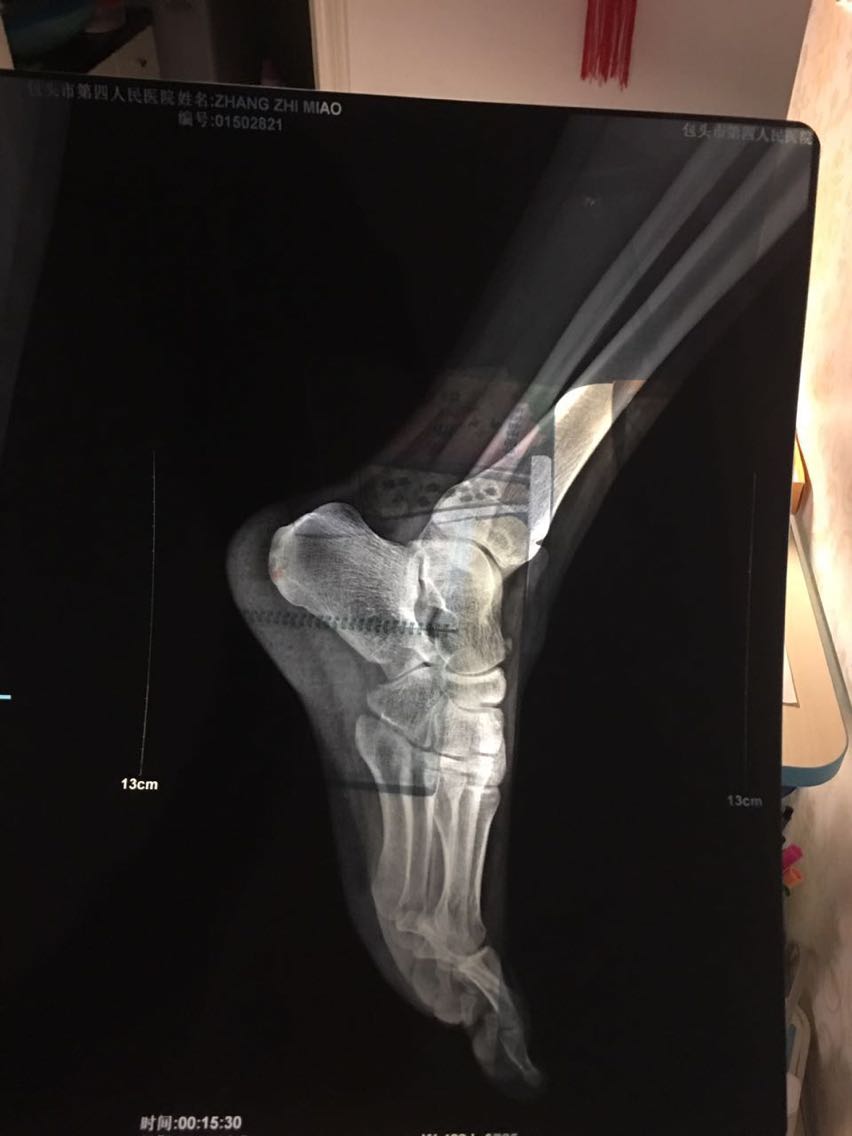

查体:左足踝及足部软组织略肿胀,中后足背侧体表可见突起肿物,质硬,无移动度,触压痛阳性,叩击Tinel征阳性,足位于跖屈内翻位时,症状加重(这一活动可使腓浅神经张力增高,更易激惹)。 辅查:足部侧位片可见距骨上缘外生骨疣(刺激腓浅神经)。